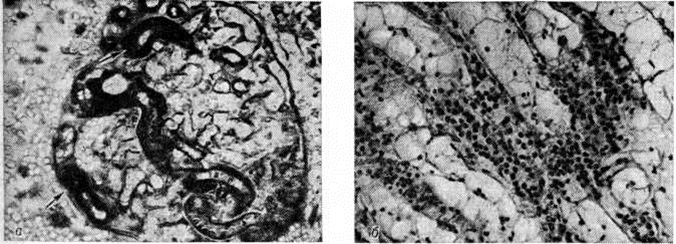

Патологическая анатомия. Морфологически изменения почек при острой Почечная недостаточность зависят от этиологии, периода болезни, своевременности, характера и объёма лечебный мероприятий. Макро и микроскопическая картина ишемических изменений почек, или так называемый шоковая почка (побледнение коркового вещества при полнокровии юкстамедуллярной зоны), чаще наблюдается при травматическом шоке, кровопотере и не характерна для процессов экзо и эндотоксического происхождения. При гистологический исследовании обнаруживают очаговые поражения эпителия канальцев с преобладанием гидропической дистрофии нефроцитов (рисунок 1). Электронно-микроскопическое исследование свидетельствует о выраженном и глубоком повреждении почечных канальцев: вакуолизации цитоплазмы вследствие расширения цистерн эндоплазматической сети; отёке или набухании митохондрий с появлением хлопьевидных уплотнений и фрагментацией крист; очаговой деструкции щёточной каёмки с парциальным отёком и секвестрацией апикальных отделов цитоплазмы. Реже развивается распространённый колликвационный некроз нефроцитов извитых почечных канальцев проксимальных и дистальных отделов нефрона. Все эти повреждения сопровождаются ферментными изменениями нефроцитов. Разрыв почечных канальцев (тубулорексис) считают типичным при шоке, хотя некоторые патологи считают это артефактом. При шоке, сопровождающемся гемолизом и миолизом, морфологический изменения в почках соответствуют гемоглобинурийному и миоглобинурийному нефрозу (смотри полный свод знаний: Миоглобинурия). После инфузионной терапии морфологический картина поражения почечных канальцев может изменяться: вследствие осмотического нефроза происходит вакуолизация, увеличиваются пиноцитозные пузырьки и наступает растяжение щёточной каёмки нефроцитов. В клубочках почечных телец отмечают малокровие, слущивание отдельных эндотелиоцитов с оголением базальных мембран, иногда субэндотелиальные отложения фибрина.

Рис. 1.

Микропрепарат (а) и электронограмма (б) почки при острой почечной недостаточности (шоковая почка): а — в эпителии проксимального отдела нефрона отмечается выраженная гидропическая дистрофия нефроцитов (указаны стрелками); окраска метиленовым синим и азуром II; × 400; б — вакуолизация, парциальный отёк и секвестрация апикальных отделов цитоплазмы нефроцита; 1 — ядро, 2 — ядрышко, 3 — секвестр, 4 — просвет канальца, 5 — вакуоль, 6 — митохондрии, 7 — отёк, 8 — щёточная каёмка; × 10 000.